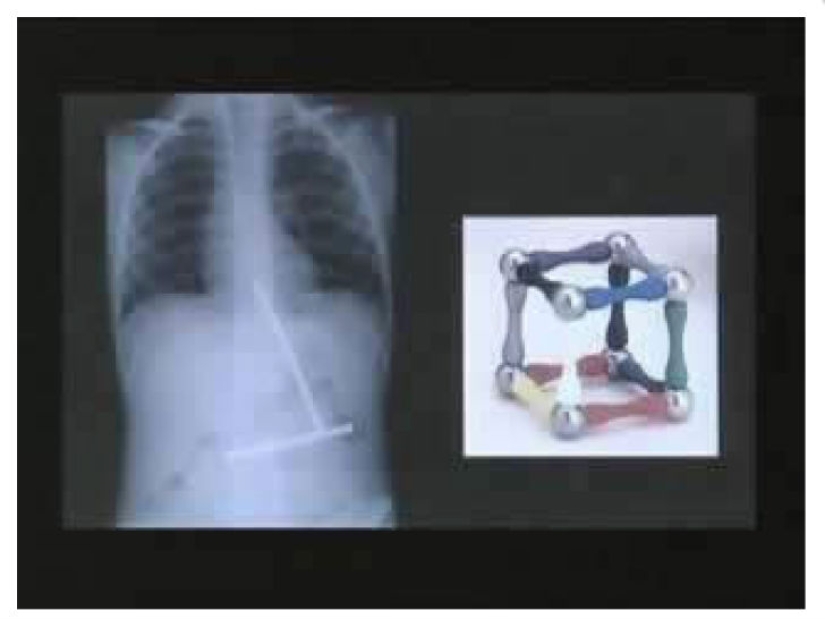

Un niño pequeño se comió una parte de un juguete con un imán a la vez. Cuando por fin todas las partes del juguete estaban en el estómago del niño, se conectaron.